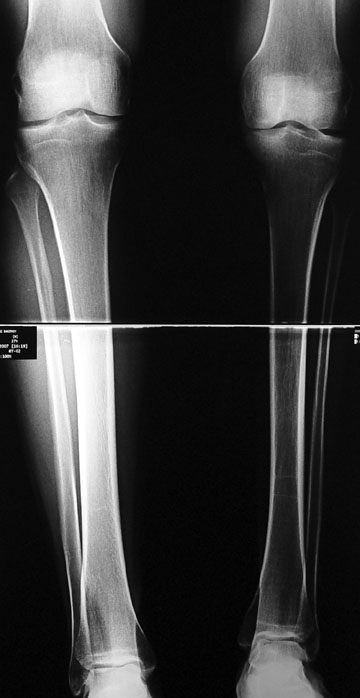

3. POSTTRAUMATIC LOWER LIMB SHORTNESS (MALUNION)

This type of shortness occurs after a fracture heals in a shortened position. Most cases are seen in adults and can be treated with one lengthening operation. Additional deformities can be corrected simultaneously. Most of these cases can be treated with lengthening over nail or just corrections and intramedullary nailing.